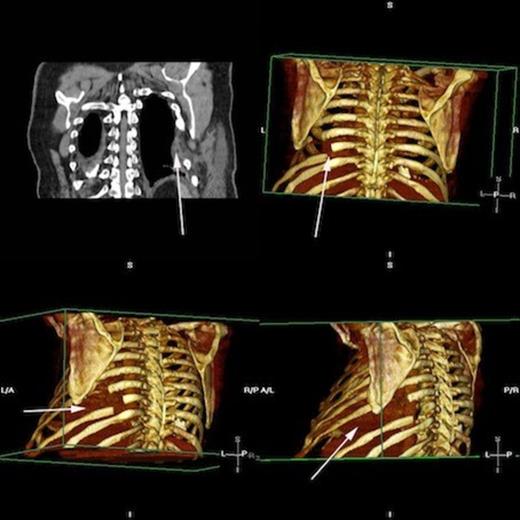

Postoperative progress was satisfactory and without complication, with the patient receiving daily input from the surgical, anaesthetic and physiotherapy teams. A repeat CT scan following the procedure confirmed restoration of the hernial defect and correction of the pulmonary hernia (figure 9).

Postoperative rendered images confirming restoration of herniated lung Top left, CT demonstrating PermacolTM patch in situ. Rendered images display areas of resected ribs and the revised bony form. Lung is restored and shows no evidence of herniation.